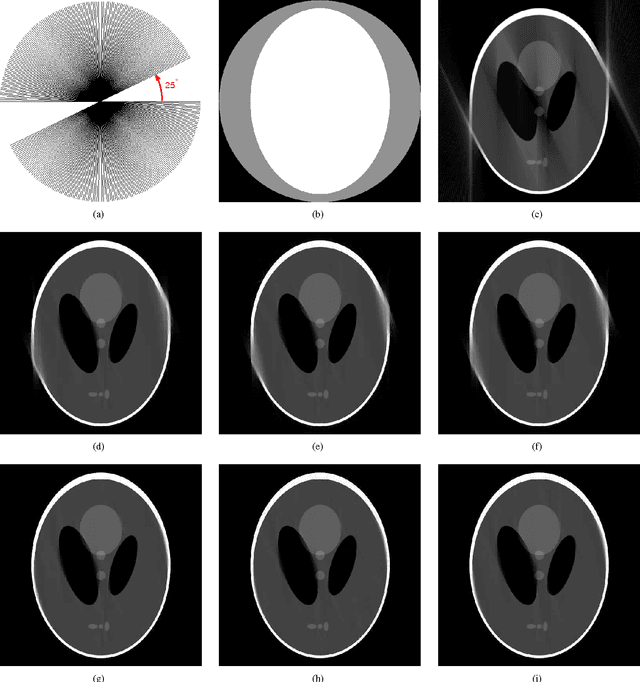

We develop mask iterative hard thresholding algorithms (mask IHT and mask DORE) for sparse image reconstruction of objects with known contour. The measurements follow a noisy underdetermined linear model common in the compressive sampling literature. Assuming that the contour of the object that we wish to reconstruct is known and that the signal outside the contour is zero, we formulate a constrained residual squared error minimization problem that incorporates both the geometric information (i.e. the knowledge of the object's contour) and the signal sparsity constraint. We first introduce a mask IHT method that aims at solving this minimization problem and guarantees monotonically non-increasing residual squared error for a given signal sparsity level. We then propose a double overrelaxation scheme for accelerating the convergence of the mask IHT algorithm. We also apply convex mask reconstruction approaches that employ a convex relaxation of the signal sparsity constraint. In X-ray computed tomography (CT), we propose an automatic scheme for extracting the convex hull of the inspected object from the measured sinograms; the obtained convex hull is used to capture the object contour information. We compare the proposed mask reconstruction schemes with the existing large-scale sparse signal reconstruction methods via numerical simulations and demonstrate that, by exploiting both the geometric contour information of the underlying image and sparsity of its wavelet coefficients, we can reconstruct this image using a significantly smaller number of measurements than the existing methods.